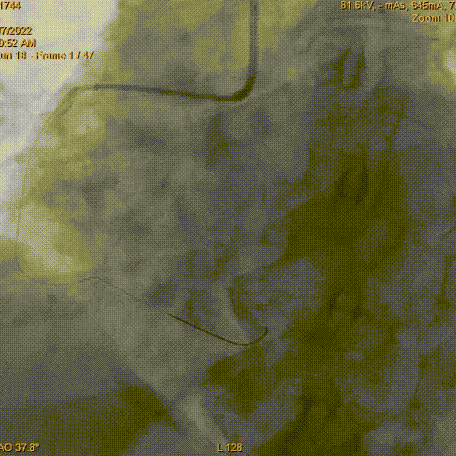

2.75×16mm Vesselin药物球囊

以12atm×40s充分扩张

最终造影结果

冠脉迂曲病变器械通过困难,处理过程中应用Telescope™导引延长导管可以有效提供额外支撑,同时对于药物球囊使用在Telescope™导引延长导管的辅助作用下可以加快药物球囊的输送速度,最大化药物局部释放疗效,取得良好的临床结果。